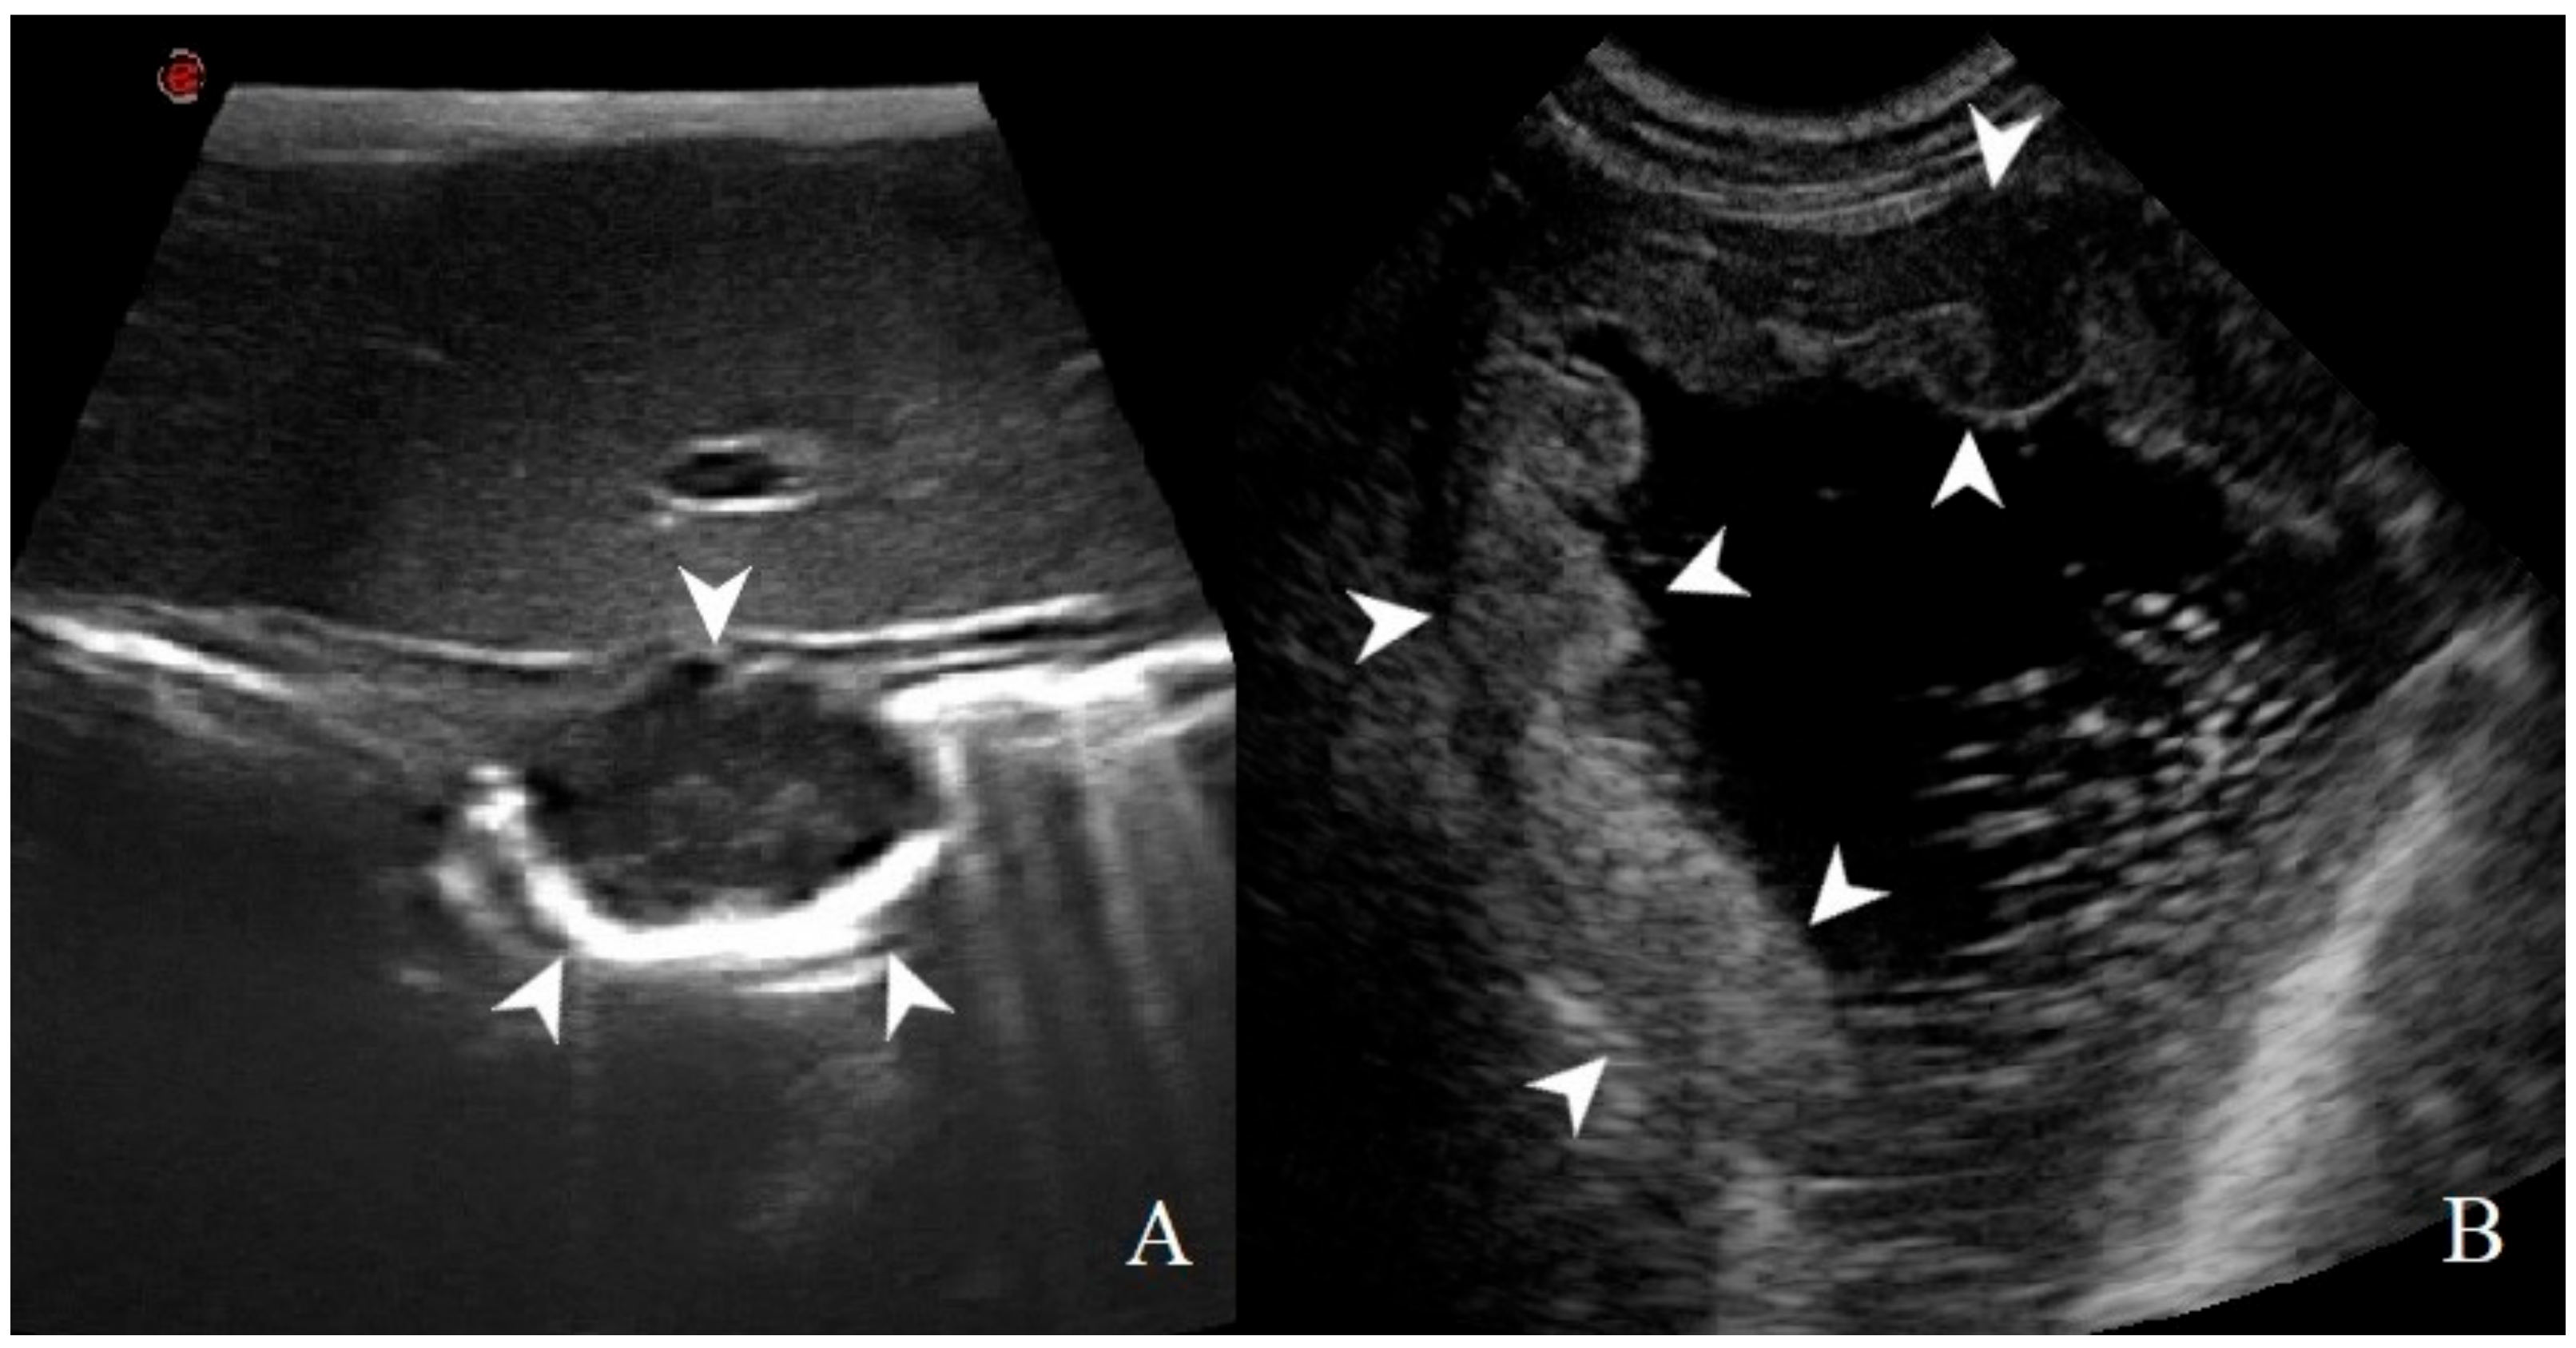

3.2. Analysis of B-Mode Examination